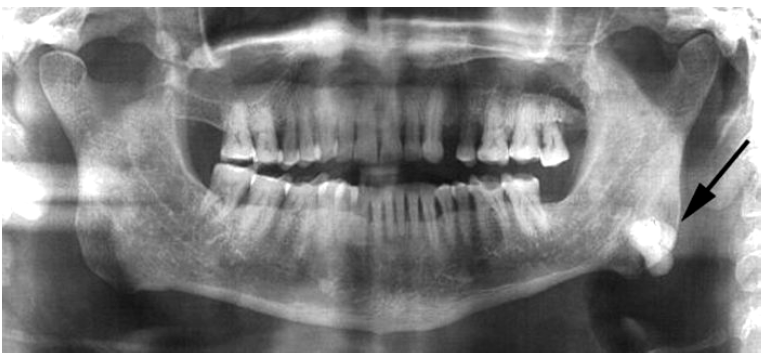

idiopathic osteosclerosis

a focal area of increased bone density that cannot be attributed to any specific cause

teens and young adults

mandible (90% of cases) : premolar and 1st molar area

adjacent teeth are vital

idiopathic osteosclerosis differential diagnosis

contrast with condensing osteitis

if the tooth is non vital - condensing osteosis

condensing osteitis

features of condensing osteitis

non-vital tooth or presence a source of inflammation

widened PDL

sclerosis of bone around roots in response to chronic inflammation

may mimic idiopathic osteoscerosis